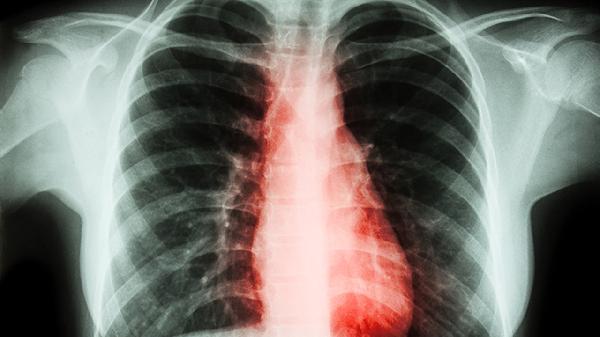

当胸椎黄韧带增厚导致脊髓或神经根严重受压时,手术是必要选择。典型症状包括进行性下肢无力、踩棉花感、大小便功能障碍等。影像学检查若显示椎管狭窄率超过50%,或动态位MRI证实韧带肥厚造成脊髓动态受压,需考虑椎板切除减压术、黄韧带切除术等。术后需配合康复训练预防粘连,如神经松动术、渐进性抗阻运动。合并骨质疏松者还需同步抗骨质疏松治疗,如阿仑膦酸钠维D3片、碳酸钙D3颗粒,以降低邻近节段退变风险。